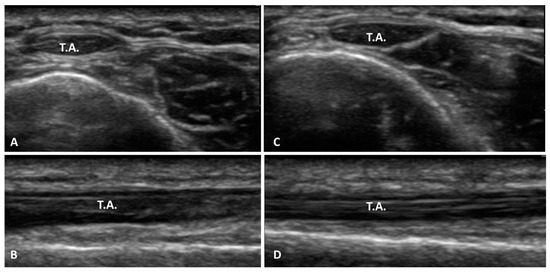

- Bianchi, S.; Becciolini, M. Ultrasound Features of Ankle Retinacula: Normal Appearance and Pathologic Findings. J. Ultrasound Med. 2019, 38, 3321–3334. [Google Scholar] [CrossRef]

- Pirri, C.; Stecco, A.; Stecco, C.; Özçakar, L. Ultrasound imaging and Fascial Manipulation: ’Adding a twist‘ on the ankle retinacula. J. Bodyw. Mov. Ther. 2024, 37, 90–93. [Google Scholar] [CrossRef] [PubMed]

- Pirri, C.; Stecco, A.; Stecco, C.; Özçakar, L. Ultrasound imaging and Fascial Manipulation for rigid retinacula in two cases of complex regional pain syndrome. Med. Ultrason. 2022, 24, 372–374. [Google Scholar] [CrossRef] [PubMed]

- Pirri, C.; Stecco, C.; Güvener, O.; Mezian, K.; Ricci, V.; Jačisko, J.; Fojtik, P.; Kara, M.; Chang, K.V.; Dughbaj, M.; et al. EURO-MUSCULUS: European Musculoskeletal Ultrasound Study Group in Physical and Rehabilitation Medicine. EURO-MUSCULUS/USPRM Dynamic Ultrasound Protocols for Ankle/Foot. Am. J. Phys. Med. Rehabil. 2024, 103, e29–e34. [Google Scholar] [CrossRef] [PubMed]